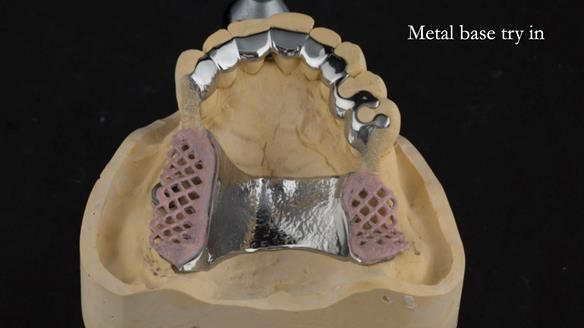

A metal-based upper RPD was made,

with metal backings incorporated to future-proof the design

should further teeth fail.

Looking back, we would make this denture more hygienic now. The design and finish would be more refined and delicate, particularly when compared with the upper metalwork, which was made later using Chris Hesketh’s chrome work. I will discuss this in detail at the study club.